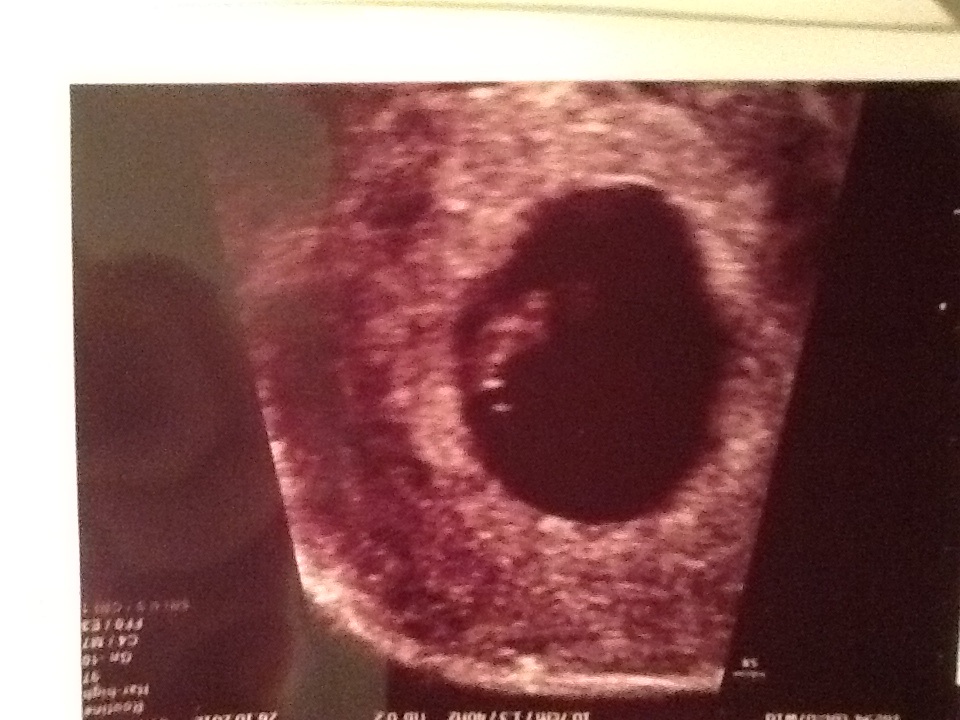

FEMALE- LEFT SIDE

Attachment 2065